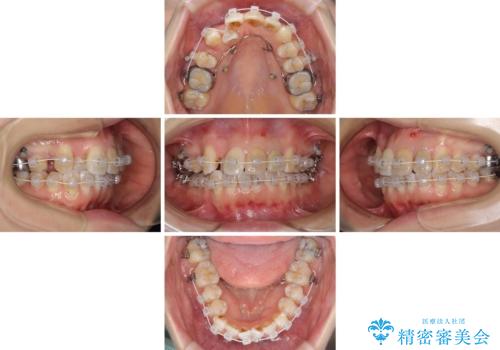

- 審美装置

- 1年7ヶ月

- 10-30回

右上4番目の歯を抜歯し、上顎裏側に補助装置を装着して左の歯列全体を後方に移動させながら、正中を合わせるようにして行くこととしました。